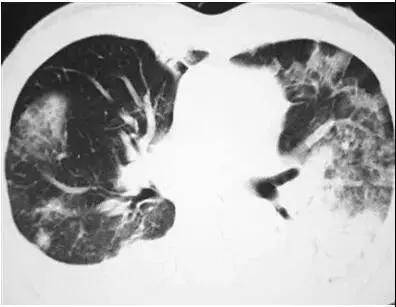

如何从肺CT上看人品、看艾滋病

439x313 - 28KB - JPEG

512x360 - 35KB - JPEG